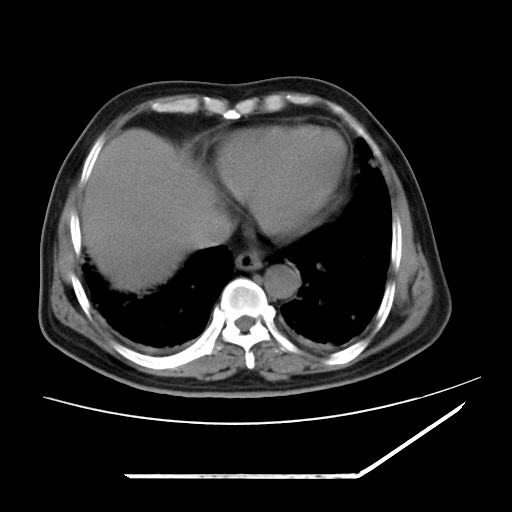

男,57,畏寒,发热

两肺野多发大小不一高密度灶,纵膈内见肿大淋巴结,要考虑转移瘤可能。双侧胸腔少量积液。

双肺多发结节样病灶,部分内见透光区,纵隔内见淋巴结肿大。结核临床如有畏寒,高热,白细胞增高首先考虑迁徙性肺脓肿(多是金黄色葡萄球菌感染)。

注意除外转移瘤。

1)考虑两肺感染性病变(金黄色葡萄球菌肺炎?);建议抗炎治疗后复查排除其他。2)双侧少量胸腔积液。